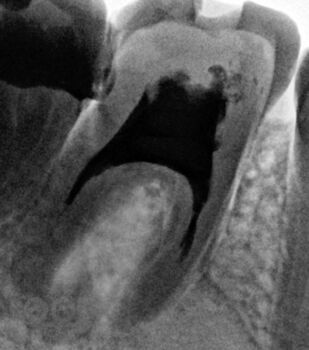

В учебно-методическом пособии представлены существующие классификации ошибок при лечении осложненного кариеса зубов. Проанализированы основные причины, приводящие к возникновению ошибок при диагностике, механической и медикаментозной обработке и обтурации корневых каналов. Рассмотрены методы предупреждения наиболее часто встречающихся осложнений эндодонтического лечения.